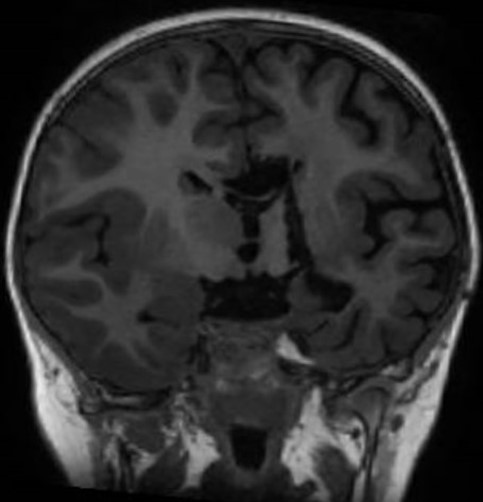

A hemisferotomia consiste em um procedimento de desconexão de segmentos específicos do cérebro com o objetivo de impedir a propagação da crise convulsiva. Ela é indicada para casos de epilepsia refratária ao tratamento medicamentoso e quando o foco da crise é localizado em um único hemisfério cerebral.

A investigação pré-cirúrgica deve demonstrar a origem unilateral e hemisférica das crises, correlacionada com EEG ou vídeo-EEG e uma ressonância de crânio compatíveis. A repercussão da epilepsia deve ser fortemente relacionada com a qualidade de vida e com a cognição (por esta razão, testes neuropsicológicos são necessários). As consequências pós cirúrgicas são ligadas à hemiparesia, hemianopsia e distúrbio cognitivo. Por esta razão, em caso de qualquer dúvida ou divergência entre exames ou entre os pares (neurologista, psicólogo), a indicação é desconsiderada e novos exames, como implantação de eletrodos cranianos por estereotaxia (S-EEG) pode ser proposta.

A técnica cirúrgica visa isolar o córtex patológico, desconectando o hemisfério cerebral doente, ao seccionar as vias de associação inter-hemisféricas (corpo caloso, comissura anterior), as conexões tálamo-corticais e dos gânglios da base, as vias de projeção (braço anterior, joelho e braço posterior da cápsula interna) e as estruturas límbicas (fornix e amigdala). A abordagem cirúrgica varia de acordo com a preferência do cirurgião, mas todas passam por acessar o sistema ventricular, via transylviana peri-insular ou sagital, inter-hemisférica (preferência deste que descreve).